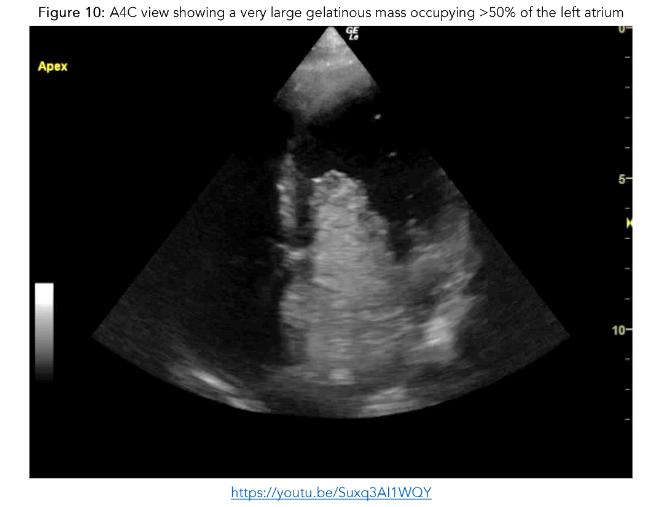

The boy was re-examined by a senior clinician following the initial survey and was noted to have a grade 3/6 ejection systolic murmur. Point of care echocardiogram was performed revealing a very large gelatinous mass occupying >50% of the left atrium.

While in ED he developed a work of breathing and became hypoxic. Point of care echocardiography was repeated and showed a distended and plethoric IVC, with innumerable B-lines anteriorly.

His symptoms rapidly resolved with a stat dose of intravenous furosemide. On transfer to PICU, he became hypotensive secondary to cardiac obstruction. Due to his clinical instability, he proceeded to theatre where he underwent resection of a cardiac myxoma, the mass initially identified on POCE in the ED. Use of POCE rapidly clarified the broader issues in this critically unwell patient with a relatively rare presentation for his age-group, additionally it guided his resuscitation and onward care accurately.

Figure 9: PLAX view showing a very large gelatinous mass occupying >50% of the left atrium